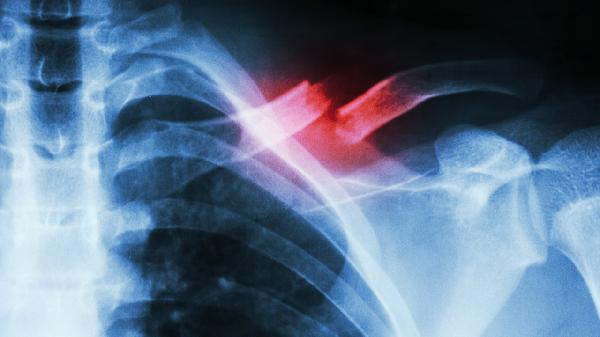

肋骨骨折合并右下肺肺不张可通过镇痛治疗、呼吸训练、物理治疗、手术治疗等方式干预。该情况通常由肋骨移位压迫肺组织、...

隐性肋骨骨折是指通过常规X线检查难以发现,但实际存在的肋骨骨折。 隐性肋骨骨折通常发生在肋骨受到外力作用但未完全...